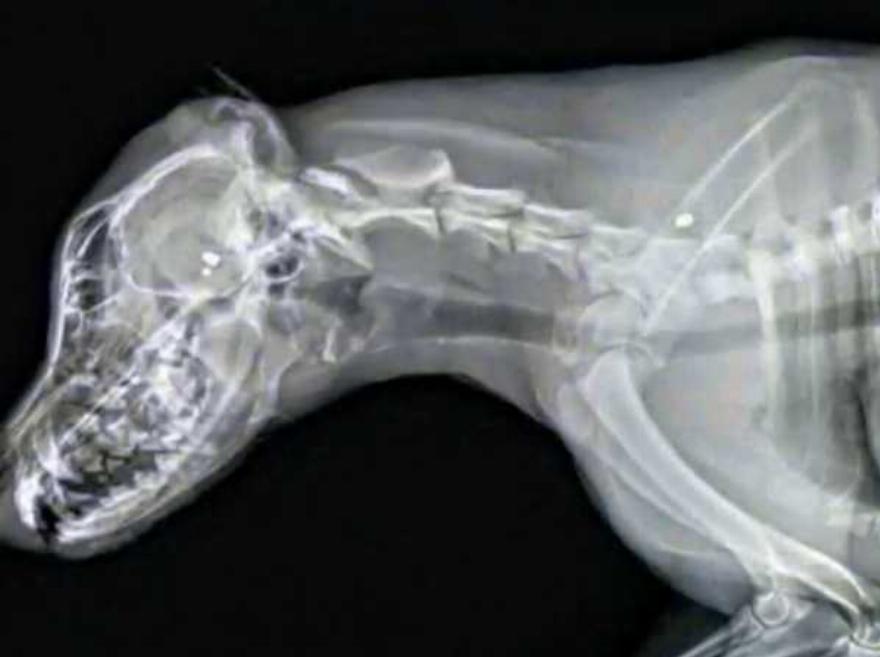

Μόλις μεταφέρθηκε στο κτηνιατριο μετά από γρήγορες εξετάσεις ο γιατρός αποκάλυψε ότι το σκυλί είχε πυροβοληθεί τρεις φορές με πιστόλι pellet.Κάτι που το πόνεσε πολύ.Ωστοσο το περίεργο ήταν πως έγινε αφού η αυλή ήταν πλήρως περιφραγμένη.

Η Abbi Taylor πήρε γνώμες από πολλούς γιατρούς αλλά λόγω του τραυματισμού και τις επιληπτικές κρίσεις που παθαίνει το σκυλί το μόνο πράγμα που μπορούσε να κάνει ήταν η ευθανασία.